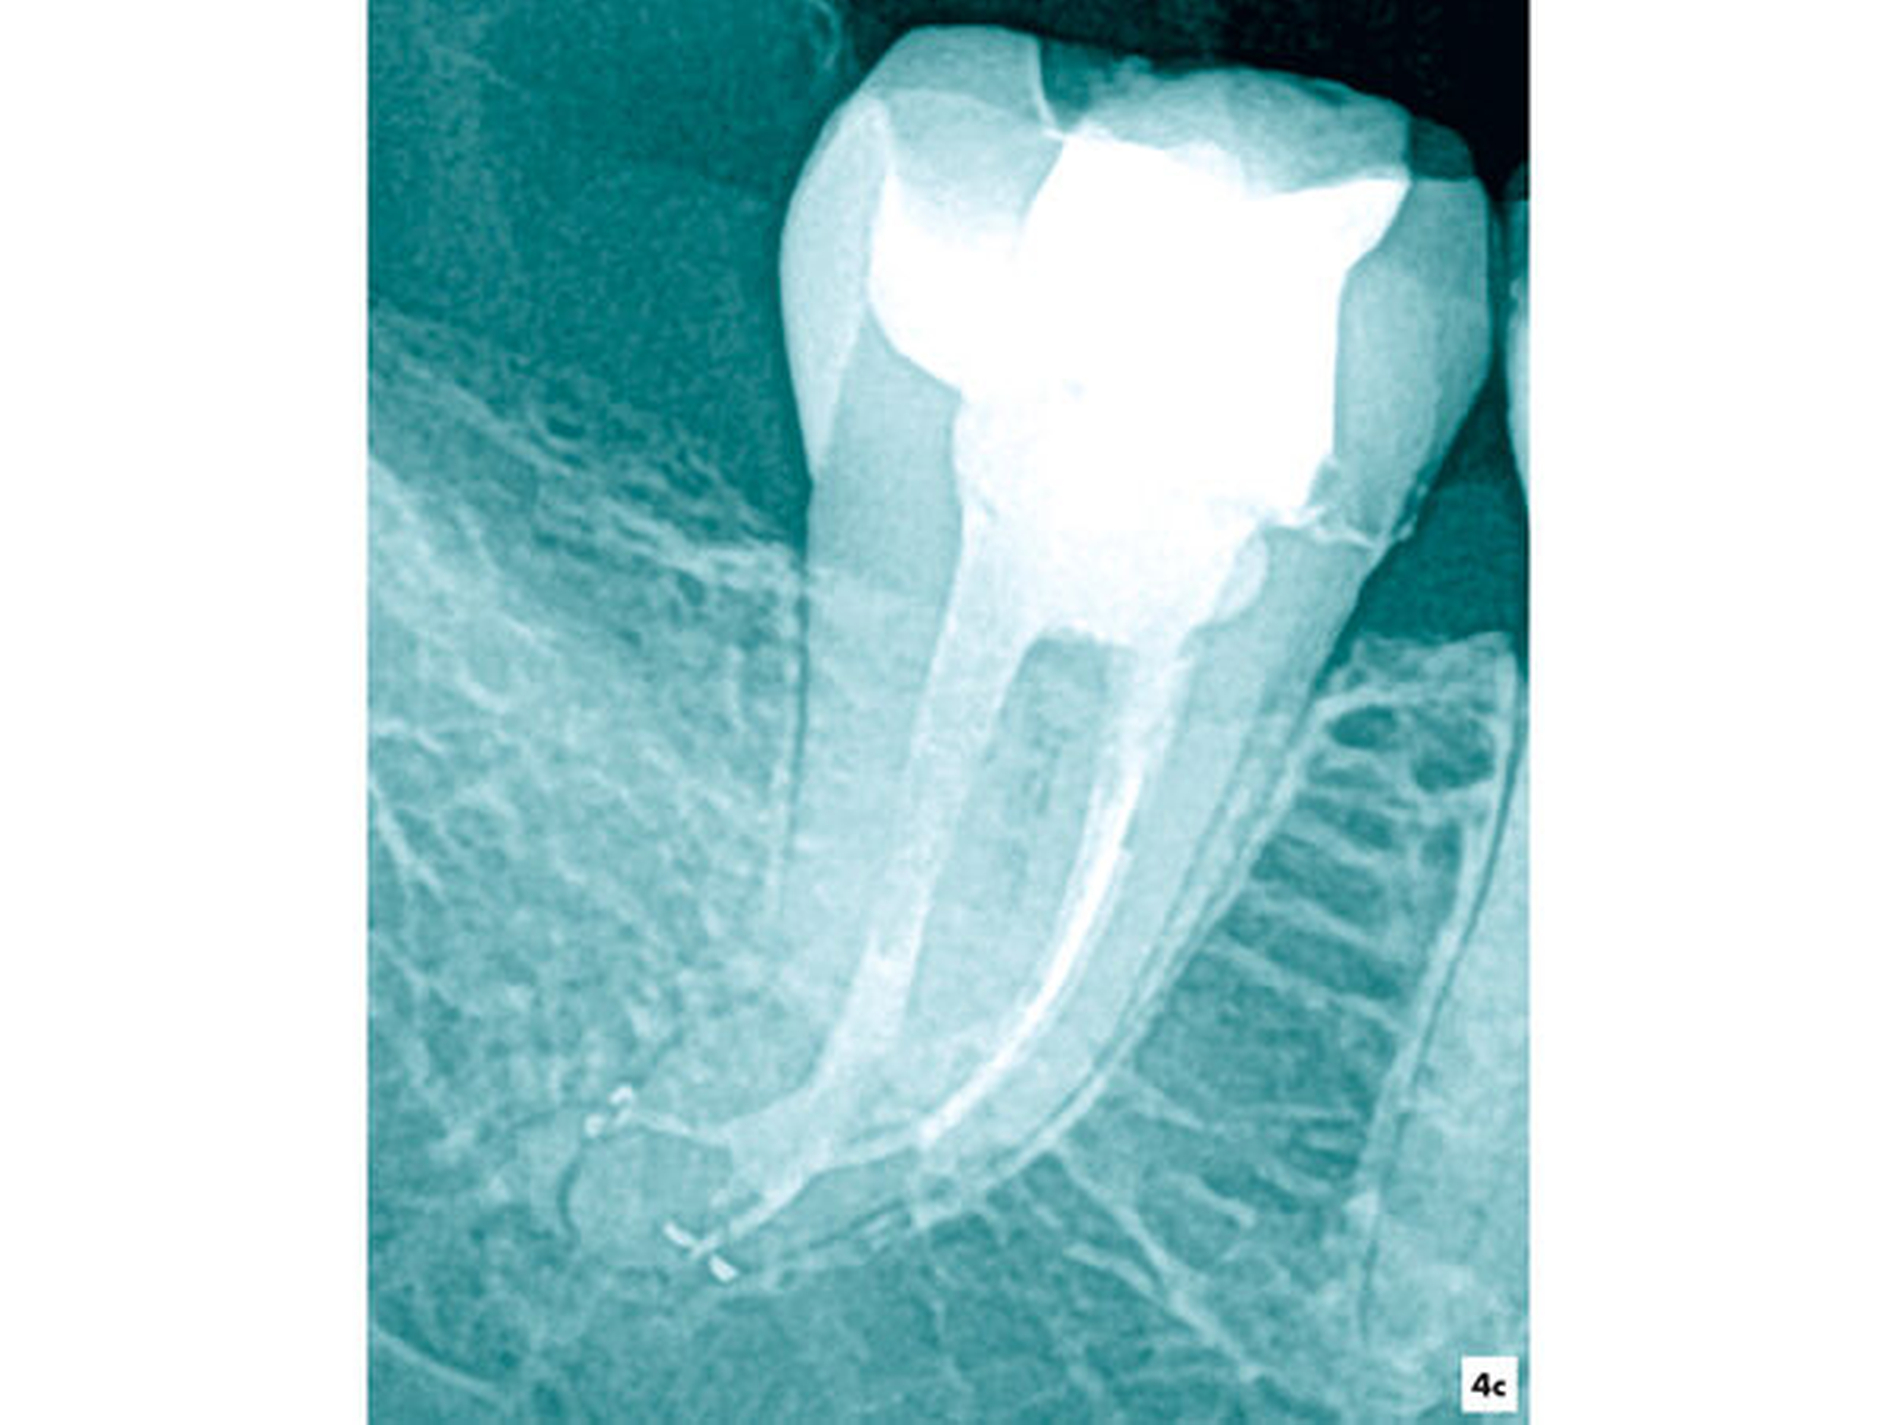

Im Verlauf der Erweiterung eines stark gekrümmten Wurzelkanalsystems kam es nach einer Vitalexstirpation am Zahn 47 zur Fraktur eines Wurzelkanalinstruments in apikaler Lage (Abbildung 4a). Unter Sicht mit dem Dentalmikroskop wurden die Wurzelkanäle bis ins apikale Wurzeldrittel mit NiTi-Feilen bis zum Fragment mechanisch erweitert. Nach einer ultraschallaktivierten Spülung und Desinfektion konnte das Fragment mit einer vorgebogenen Ultraschallfeile IrriK (VDW, München) in der Größe ISO 15 gelockert und entfernt werden, so dass eine vollständige Wurzelkanalbehandlung möglich wurde (Abbildungen 4b und 4c).